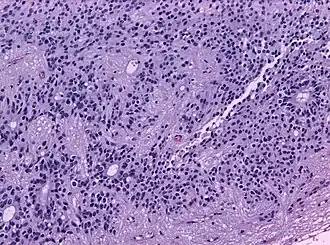

Микроскопический вид типичной нейробластомы с образованием розеток

Гистопатологический образец нейробластомы с розетками Гомера Райта, окраска гематоксилин-эозин